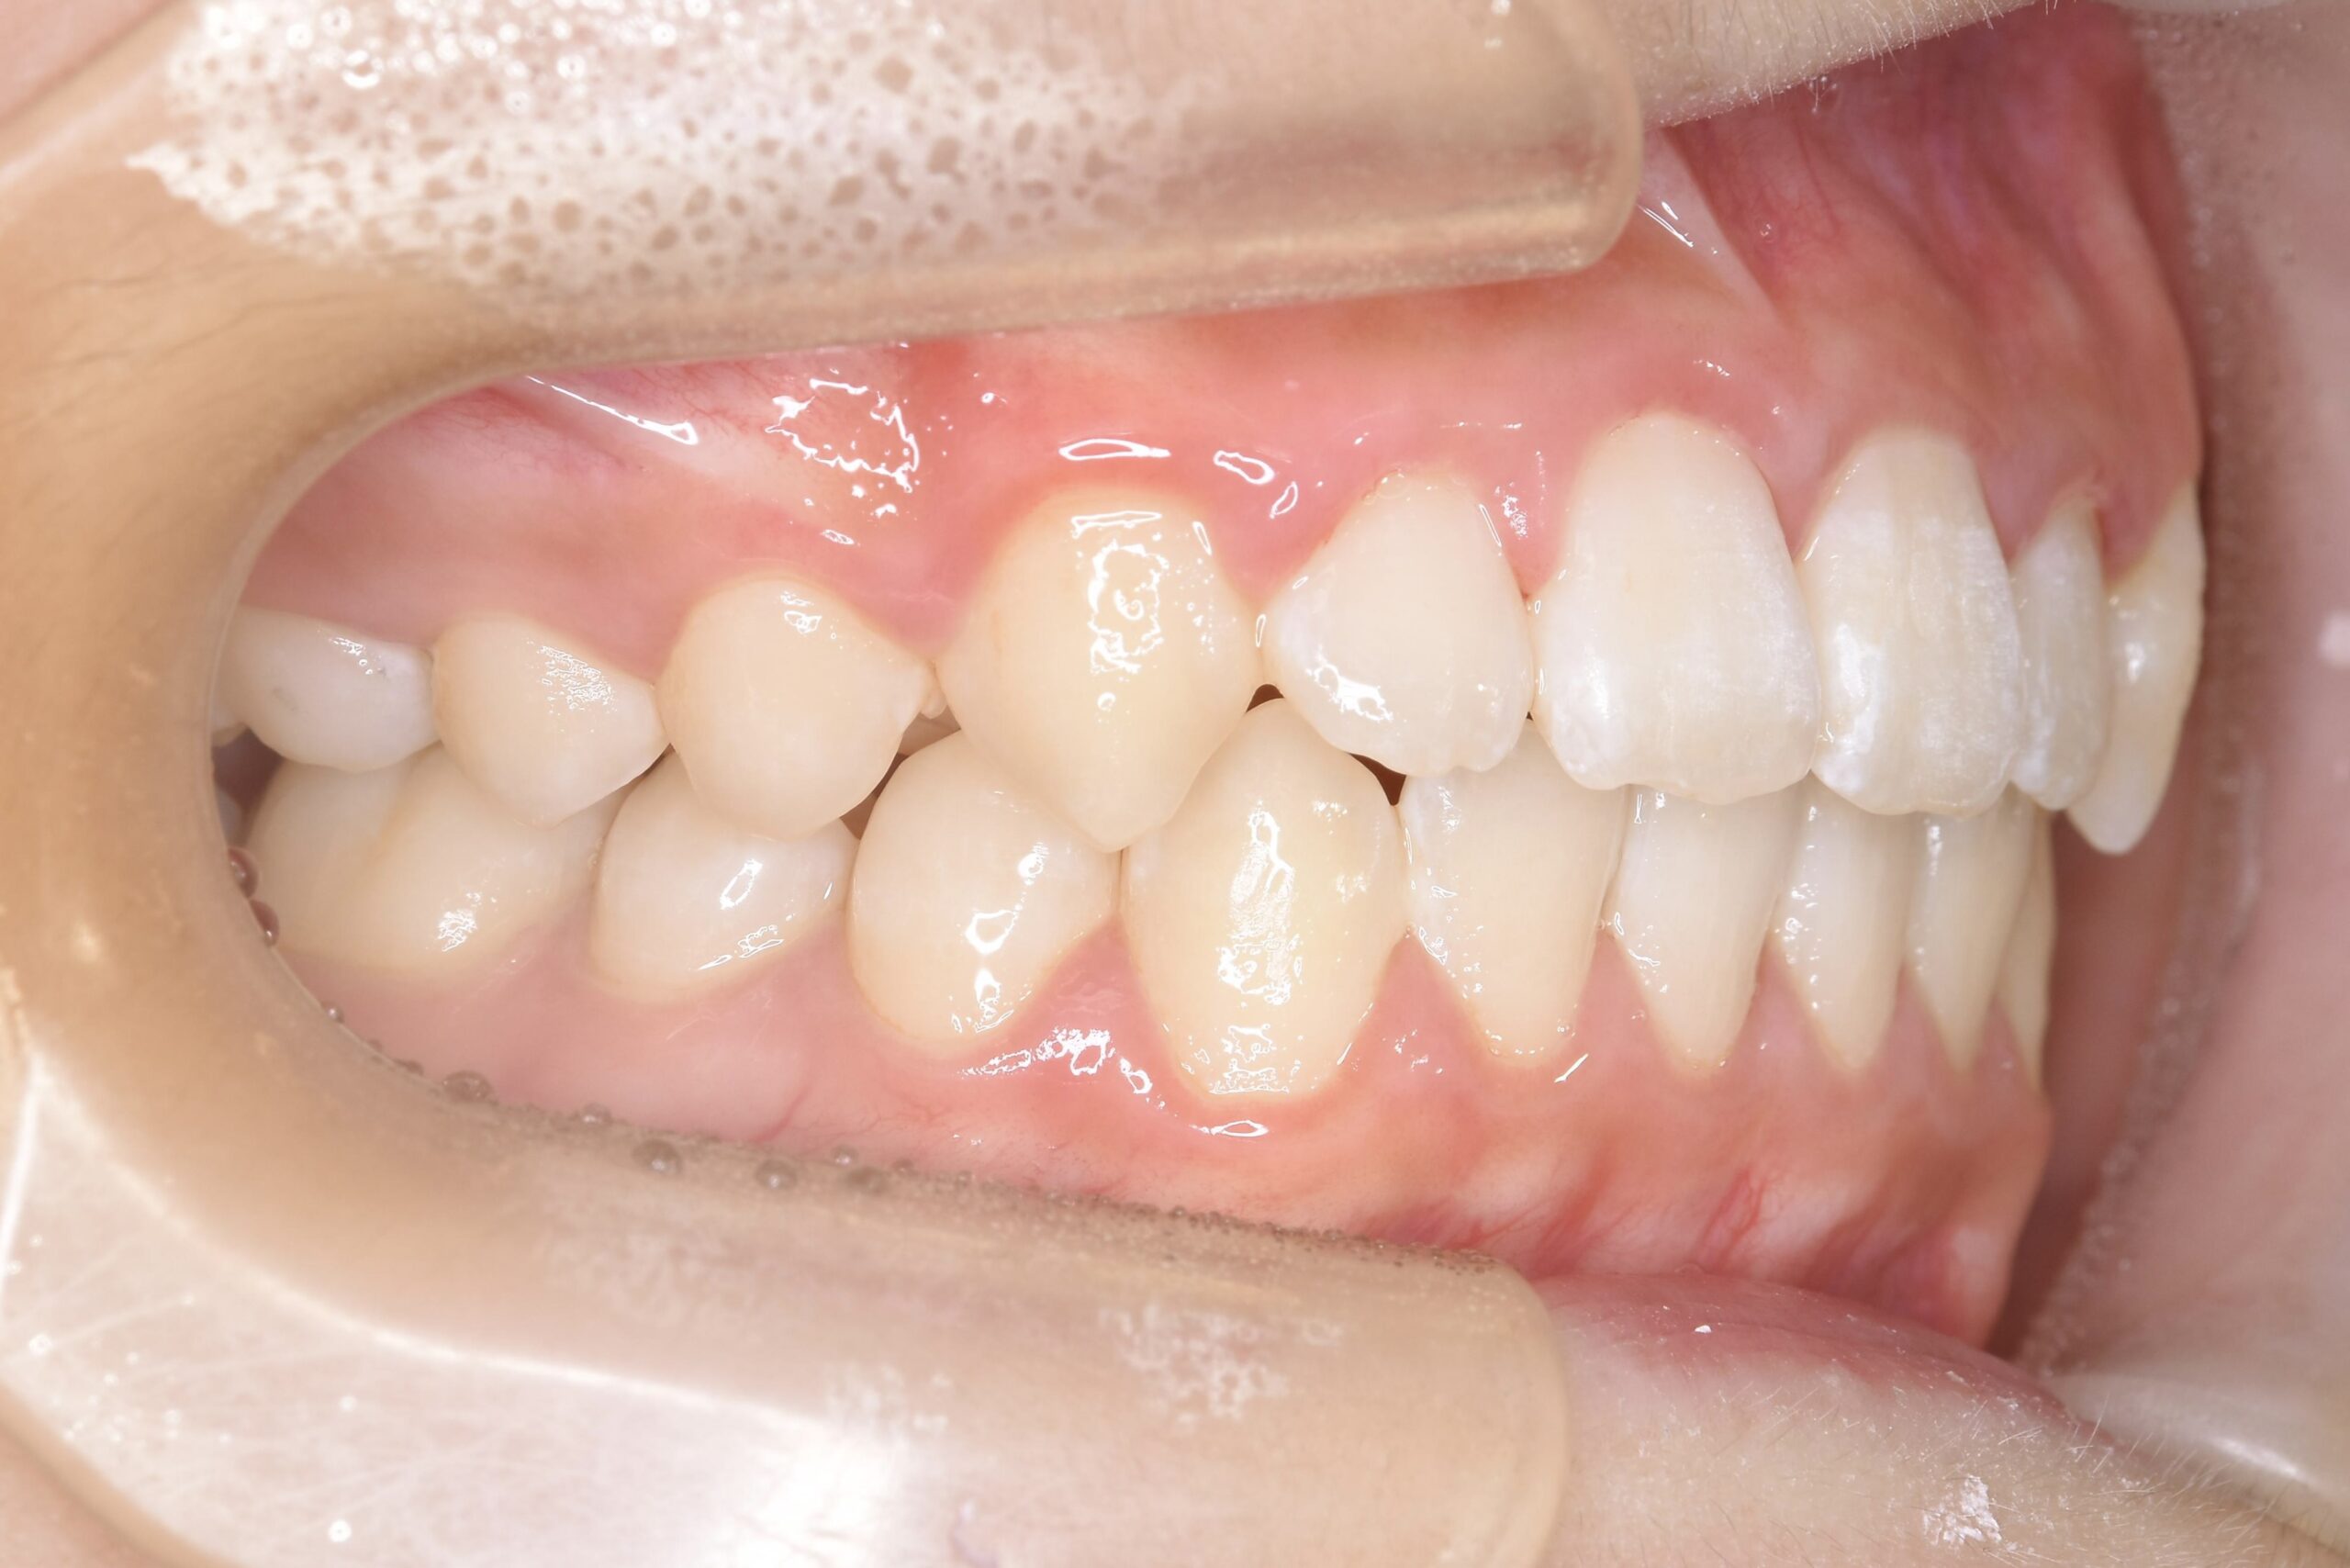

7歳 男児 小児矯正

AFTER

主訴 通っている歯医者で矯正した方がいいと言われて気になっている。下の前歯がでこぼこしている。

診断名・主な症状 下顎前歯の叢生を伴う過蓋咬合

治療内容 上下の歯並びの幅を拡げつつ、前歯の関係を改善しました。

使用装置 急速拡大装置

リンガルアーチ

機能的矯正装置(マイオブレース)

抜歯部位 抜歯なし

治療期間 2年 + 後戻り止め期間(3年 )

通院回数 20回

費用 50万円程度(税別)  29331

リスク・副作用 痛み、歯肉退縮、歯根吸収、抜歯に伴う出血や腫れが生じることがあります。